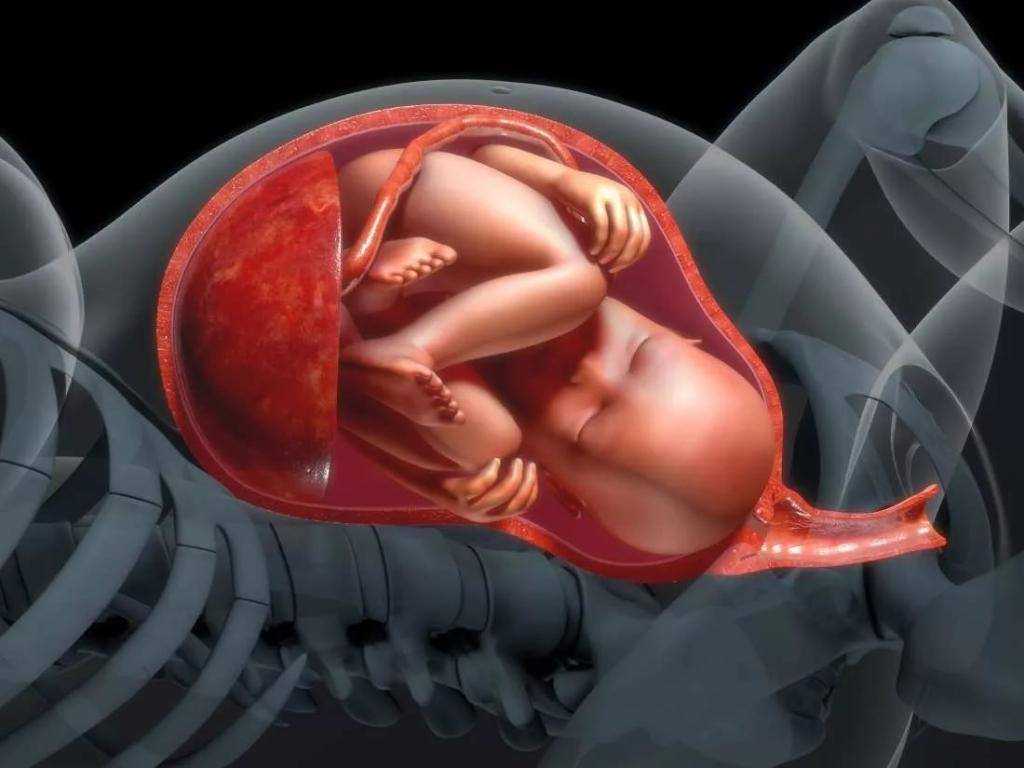

Загадочные образы животных в утробе матери